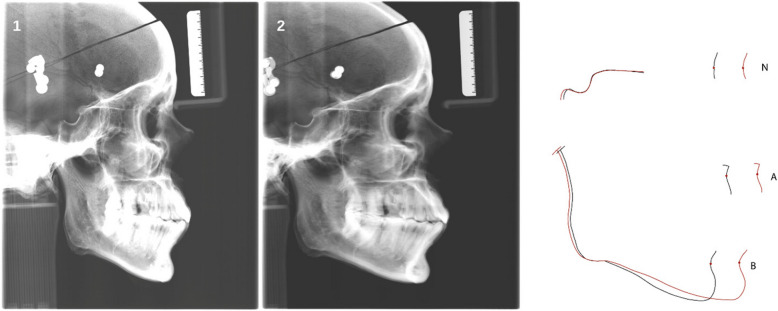

Methods: By means of a dry adult human skull and a precise motion simulation system digital Cephs are acquired while certain predefined movement patterns (shift, tilt and nodding with a motion amplitude from 5 - 50 mm) of the skull were executed. They represent the movements of children and adolescents, the main group for cephalometric radiographs.The scanning time was 9.4 s per Ceph. 10 typical landmark points of cephalometric analysis were identified by 20 observers on each Ceph twice. Using a non-motion image (Ceph0) as reference, displacement was computed as vectors relative to this image. Commonly used angles and vertical and horizontal distances were calculated.

Results: Both inter-rater as well as intra-rater-reproducibility were perfect. There was very little change in the vertical distance N-Me, in contrast to the horizontal distance S-N which showed a large variation. So patient motion parallel to the scanning direction of the fan-beam-detector unit, heavily influence distances parallel to this direction. The ANB angle and the Maxillo-Mandibular Plane Angle (ANS-PNS to Me-Go) only varied by about 1-2°.